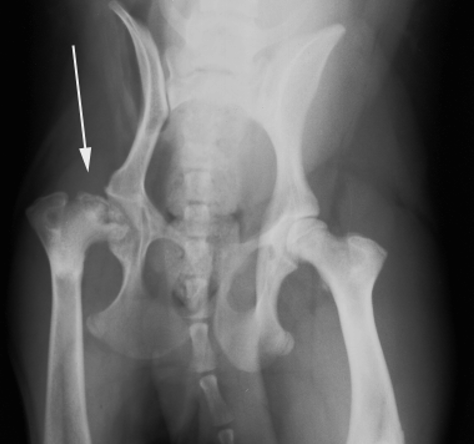

What is shown in this radiograph?

A

-normal right hip

-aseptic necrosis of femoral head in left hip